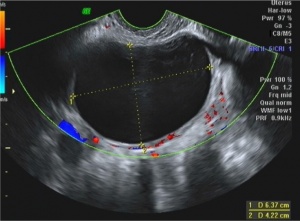

File:double_decidual_sac_sign.jpg|Double decidual sac sign | |||

- Double decidual sac sign

- Two concentric rings (uterine lining and gestation lining) around anechoic gestational sac

- Highly suggestive of intrauterine pregnancy (before yolk sac or embryo embryo visualized

- Gestational sac